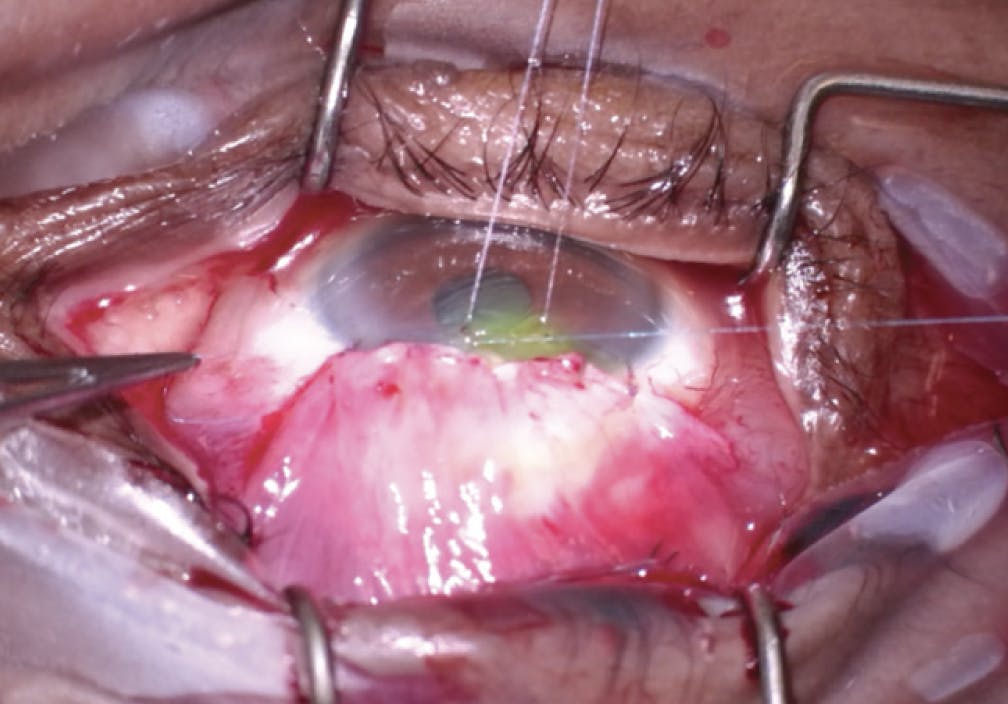

- Step No. 2: Three spaces were dissected. First, the conjunctival layer was incised linearly above the bleb space. Care was taken to free the conjunctiva from the Tenon capsule (Figure 5). Next, this capsule was dissected superior to the bleb to create a tongue of Tenon membrane (Figure 6). Finally, dissection inferiorly and under the bleb was performed to create space (Figure 7).

Figure 5. The bleb revision is initiated with dissection through and under the superior conjunctiva.